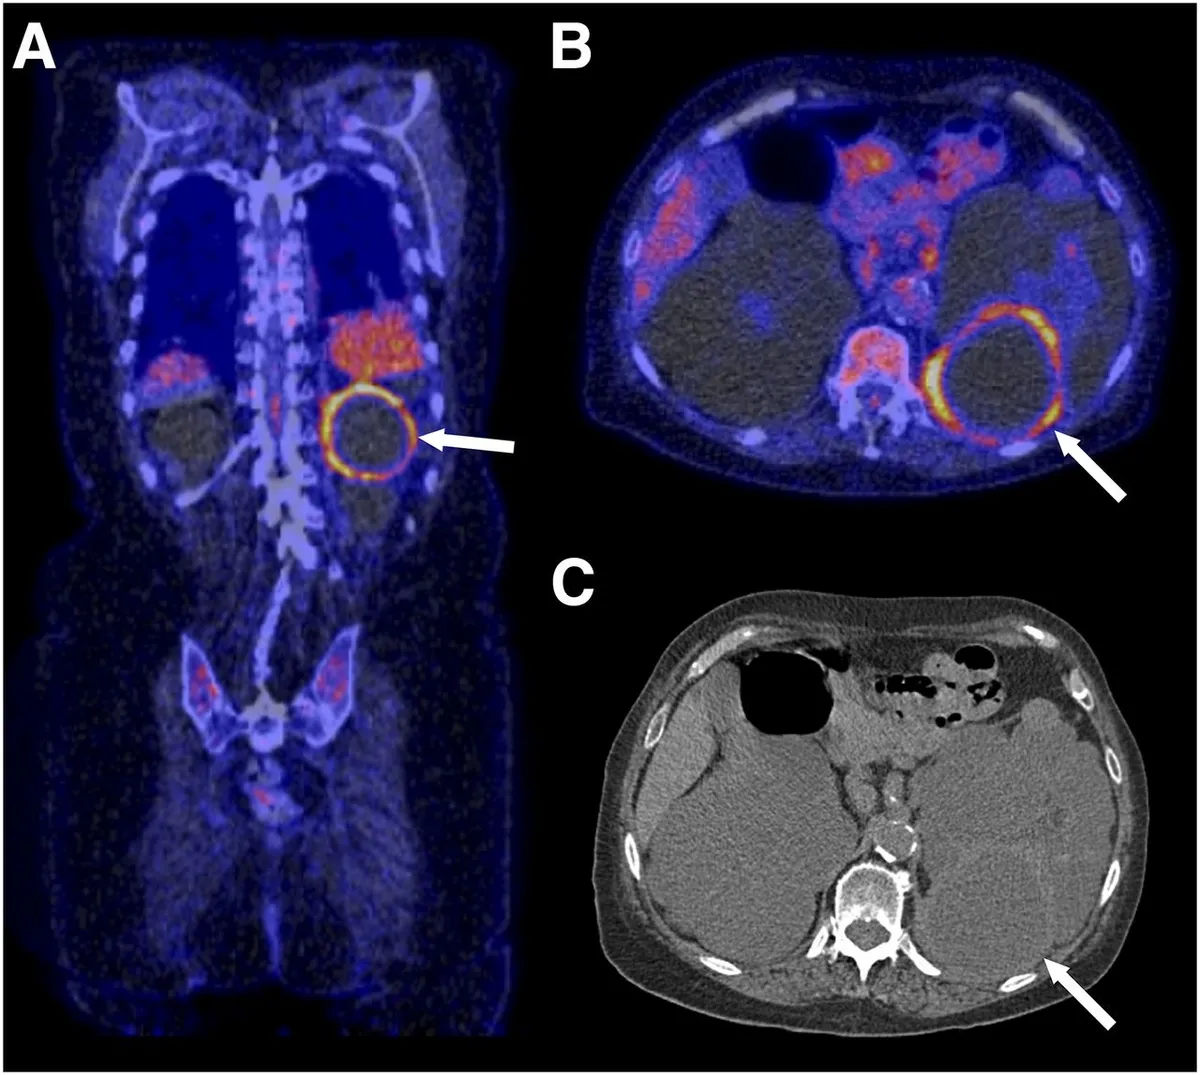

O PET/CT com 18F-FDG pode ser útil na diferenciação entre infecção de cisto renal e hepático e se destaca pela capacidade de localizar inflamações ativas.

A não resposta em até 72h ou febre persistente por mais de 7 dias após o início do antibiótico deve motivar reavaliação com TC contrastada ou PET/CT.